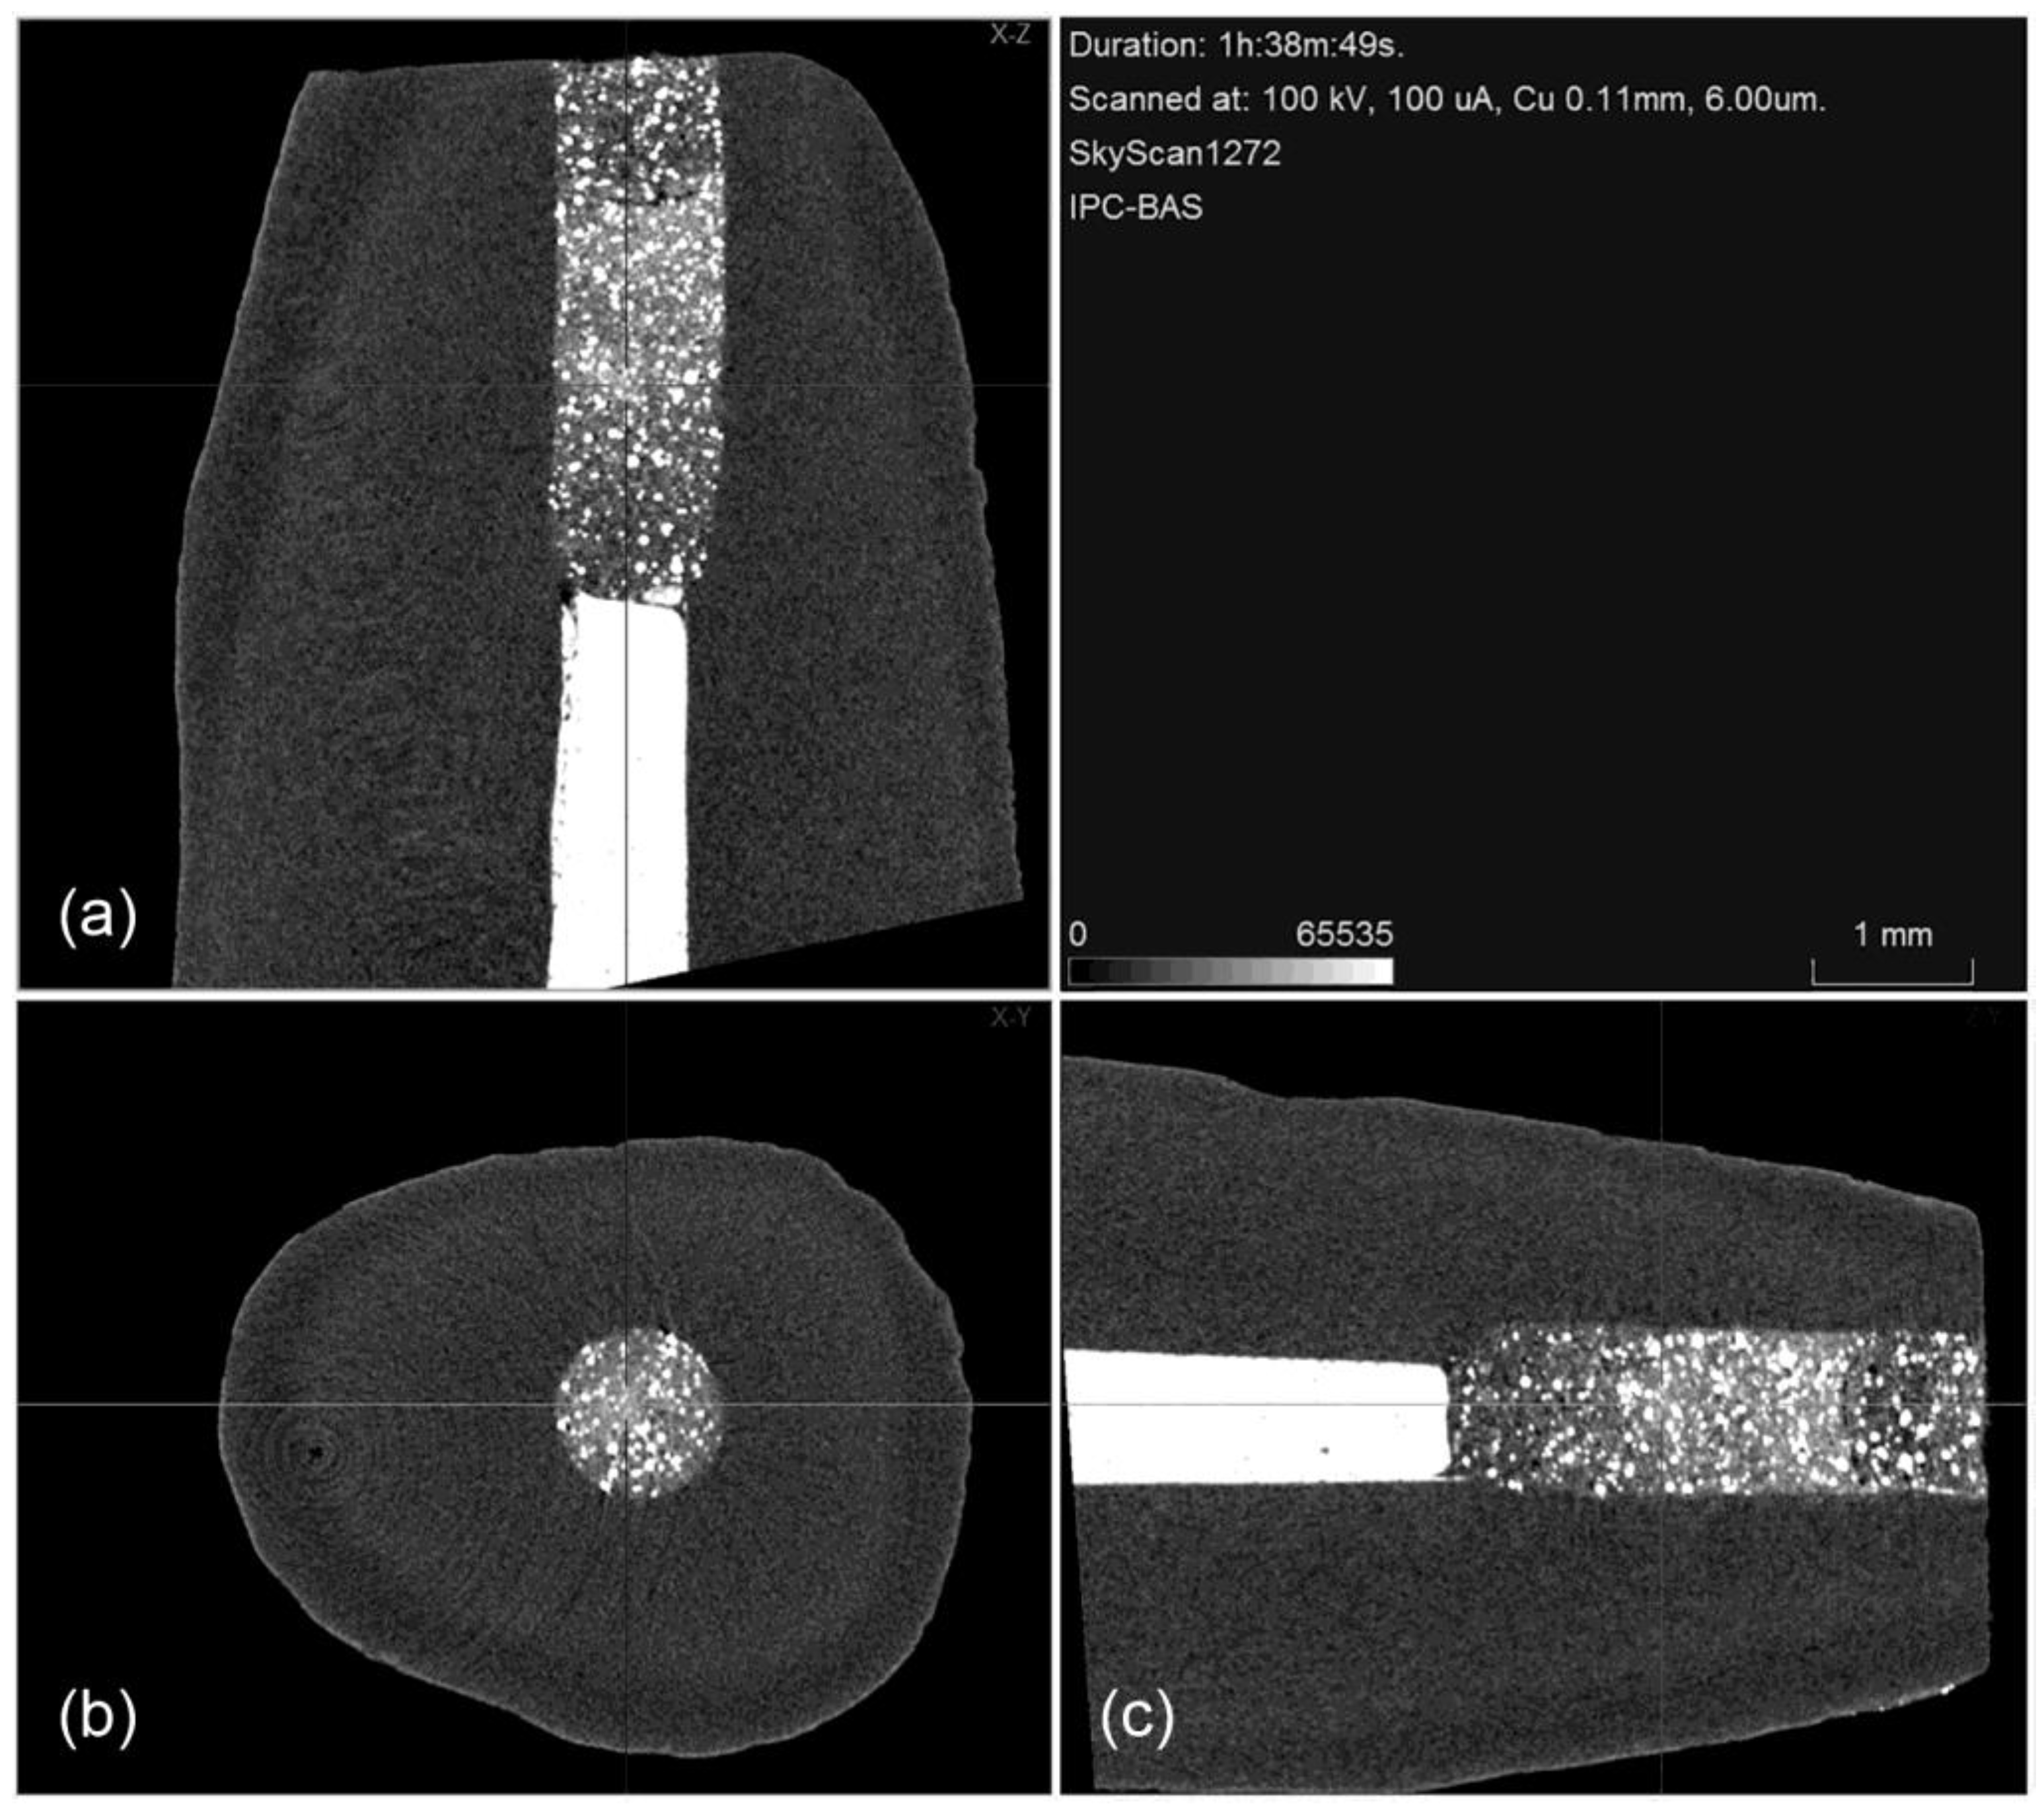

Figure 2.

Representative micro-CT cross sections showing the root-end filling of Harvard MTA at 2 mm from the apex in three planes: (a) coronal (X–Z); (b) transversal (X–Y); and (c) sagittal (Z–Y) (scale bar = 1 mm).